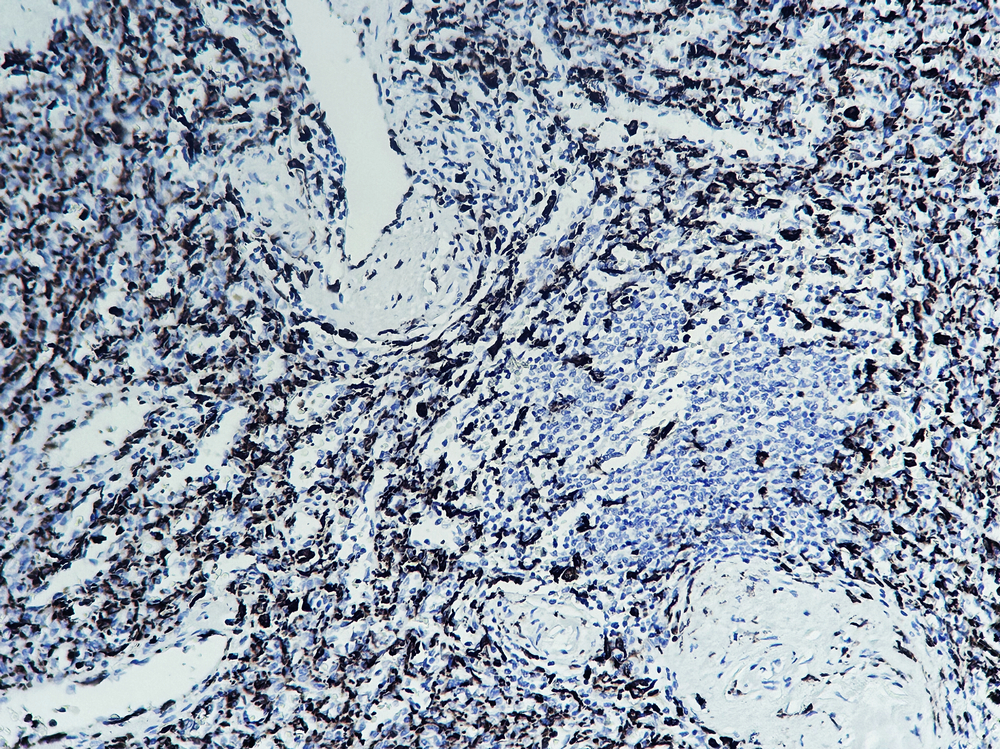

| Immunohistochemistry |

Human tonsil tissue was stained with Anti-Iba 1 (TM4765) Antibody